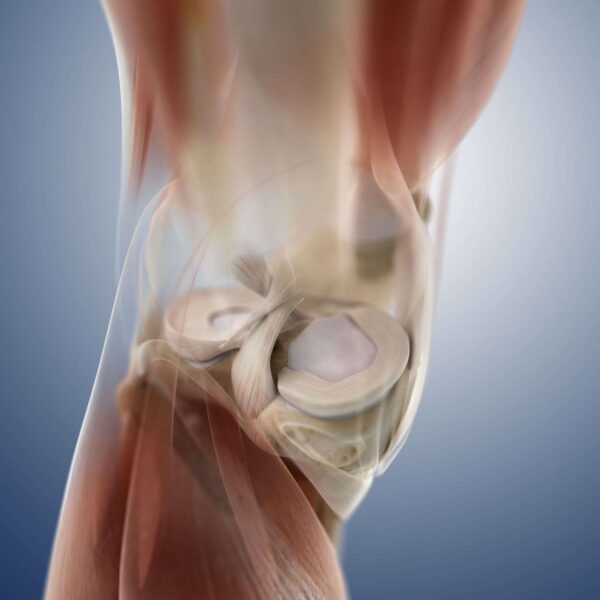

1.آناتومی زانو

زانو یکی از مفاصلی می باشد که درصد آسیب آن زیاد است. تصاویری که در ادامه مطلب خواهید دید به شما کمک خواهد کرد تا هر چه بیشتر با زانو و دردهای رایج آن آشنا شوید.

مفصل زانو، ران را به ساق پا متصل می کند. استخوان ران(femur) با استخوان ساق پا(tibia) در مفصل زانو متصل می شود. کاسه زانو(patella) در جلو مفصل زانو قرار دارد. 4 لیگامنت(رباط) اصلی استخوان ها را به هم متصل کرده و ثبات مفصل زانو را تثبیت می کند. در عکس بالا، پزشک به رباط صلیبی قدامی(جلویی) اشاره دارد که به آن ACL (مخفف anterior cruciate ligament) نیز گفته میشود که یکی از مهم ترین این لیگامنت ها می باشد.

2.آناتومی زانو

داخل مفصل زانو یک پوشش صاف در انتهای استخوان ها به نام غضروف مفصلی وجود دارد. ما بین غضروف مفصلی یک بالشتک جذب کننده شوک به اسم غضروف مینیسک وجود دارد. وقتی که مردم در مورد غضروف زانو حرف می زنند، ممکن است در مورد غضروف مینیسک یا غضروف مفصلی صحبت کنند!.